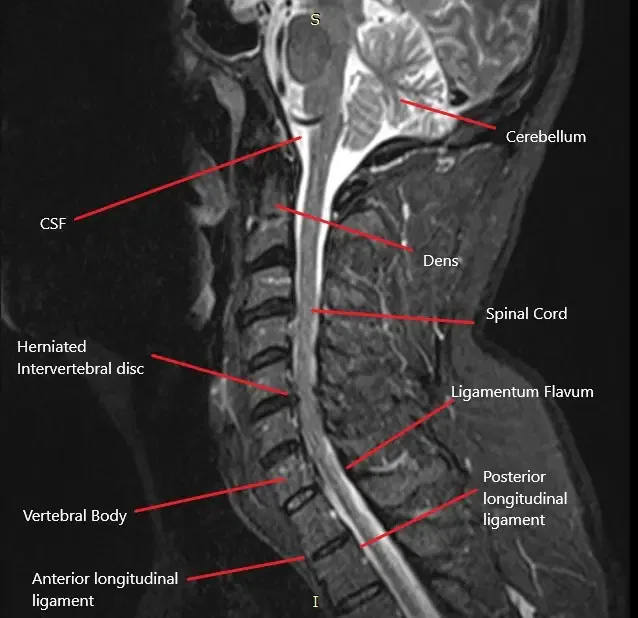

The cervical spine consists of seven vertebrae (C1-C7) in the neck region. Between each vertebra is an intervertebral disc that cushions and allows movement between the bones. The spinal cord passes through the central spinal canal, and nerves branch out from the spinal cord through the foramina (openings) in each vertebra. These nerves control sensation and movement in the shoulders, arms, hands, and other areas of the upper body. When a disc herniates, it can compress one or more of these nerves, leading to cervical radiculopathy.

- MRI: The gold standard imaging technique for identifying herniated discs, nerve compression, and other spinal abnormalities.

MRI helps visualize the herniated cervical disc and assess the extent of nerve root compression.